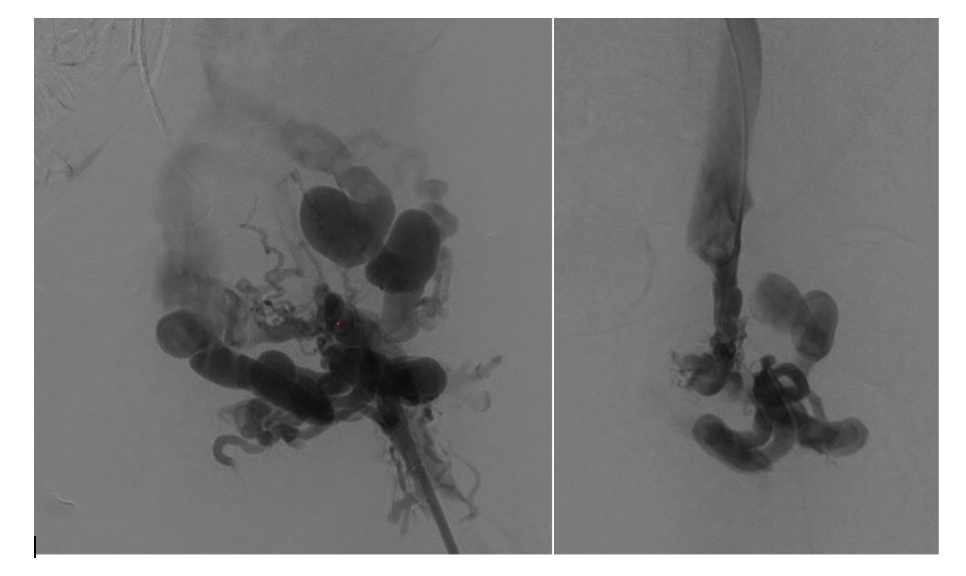

Venography was performed in multiple projections. The left groin exposure was utilized for ultrasound assessment of the target vessels. The cephalad channel appeared to parallel the left common femoral artery representing the anatomic location of the normal common femoral vein. The caudal channel was slightly deeper and posterior to the common femoral artery (Figures 3 and 4).

A 300-cm, .014-inch Fathom wire (Boston Scientific) was placed through the percutaneous needle and snared through each access sheath. With through-and-through access achieved, a direct femoral channel was established. Serial balloon angioplasty was performed with intermittent venography. Intravascular ultrasound (Philips) evaluation was also performed to document the channel. This showed a short segment of “uncovered” tract without visualization of the vein wall. At the same level, venography showed a small amount of extravasation of contrast, as expected. There continued to be filling of the large inguinal collateral veins, even after balloon dilation to 8 mm (Figure 7).